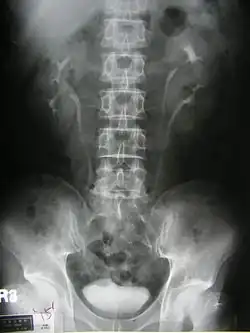

One of a series of IVP films at 15 minutes after injection of contrast medium showed incomplete duplication of left collecting system.